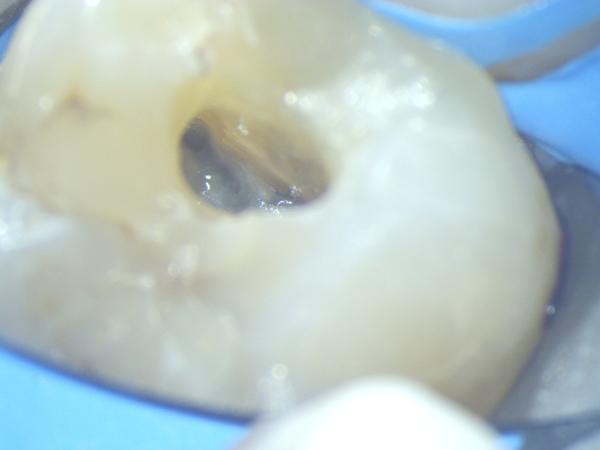

Imágenes: Endodoncia en un molar inferior izquierdo